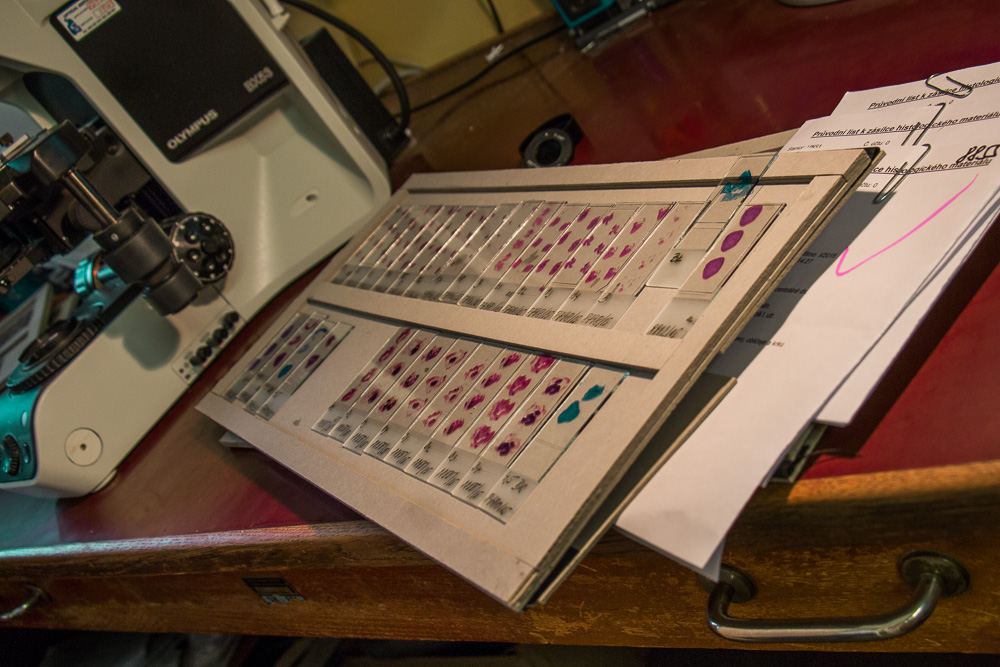

Ústav patologie a molekulární medicíny se zabývá komplexní laboratorní diagnostikou nádorových a nenádorových onemocnění. Využívá metod klasické histologie a cytologie s navazujícími dalšími speciálními laboratorními vyšetřovacími metodami. Ty zahrnují: pohled do buněk a tkání na úrovni ultrastrukturální analýzy (elektronová mikroskopie), průkaz exprese proteinů (metody imunohistochemické, Western blot, průtoková cytometrie), průkaz enzymové aktivity ve tkáňových řezech (enzymová histochemie), analýzu změn na úrovni chromozómů a genů a průkaz některých virů v histologickém řezu (metody in situ hybridizace) a rozbor DNA a RNA extrahovaných ze tkání (metody kvalitativní a kvantitativní polymerázové řetězové reakce, sekvenování). Vyšetřovaným biologickým materiálem jsou tkáně (nativní, zmrazené, fixované), punktáty kostní dřeně, periferní krev, případně jiné buněčné tekutiny (výpotky) a autologní štěpy pro transplantaci kostní dřeně.

Nosným úkolem ve zdravotnictví je zabezpečení diagnostiky a typizace chorob nemocných operovaných nebo nemocných, u kterých byly odebrány vzorky buněk nebo tkání jiným než chirurgickým operativním přístupem (endoskopické odběry, jehlové punkce, stěry buněk) ve Fakultní nemocnici Motol a Homolka. Část vyšetření probíhá v rámci takzvaných peroperačních biopsií prováděných v průběhu operace a jejichž výsledek ovlivňuje rozhodování operatéra o dalším průběhu operace. Část vyšetření prováděných na pracovišti slouží ke stanovení prognózy některých onemocnění, kontrole odpovědi onemocnění na léčbu, nebo k indikaci pro cílenou specifickou terapii pacientů. Pitevním provozem pracoviště plní edukační a kontrolní funkci v rámci Fakultní nemocnice Motol a Homolka a 2. lékařské fakulty Univerzity Karlovy v Praze.

Diagnostikou onemocnění různých systémů se zabývají týmy školených pracovníků – lékařů a biologů s pomocí laborantek ve specializovaných laboratořích.